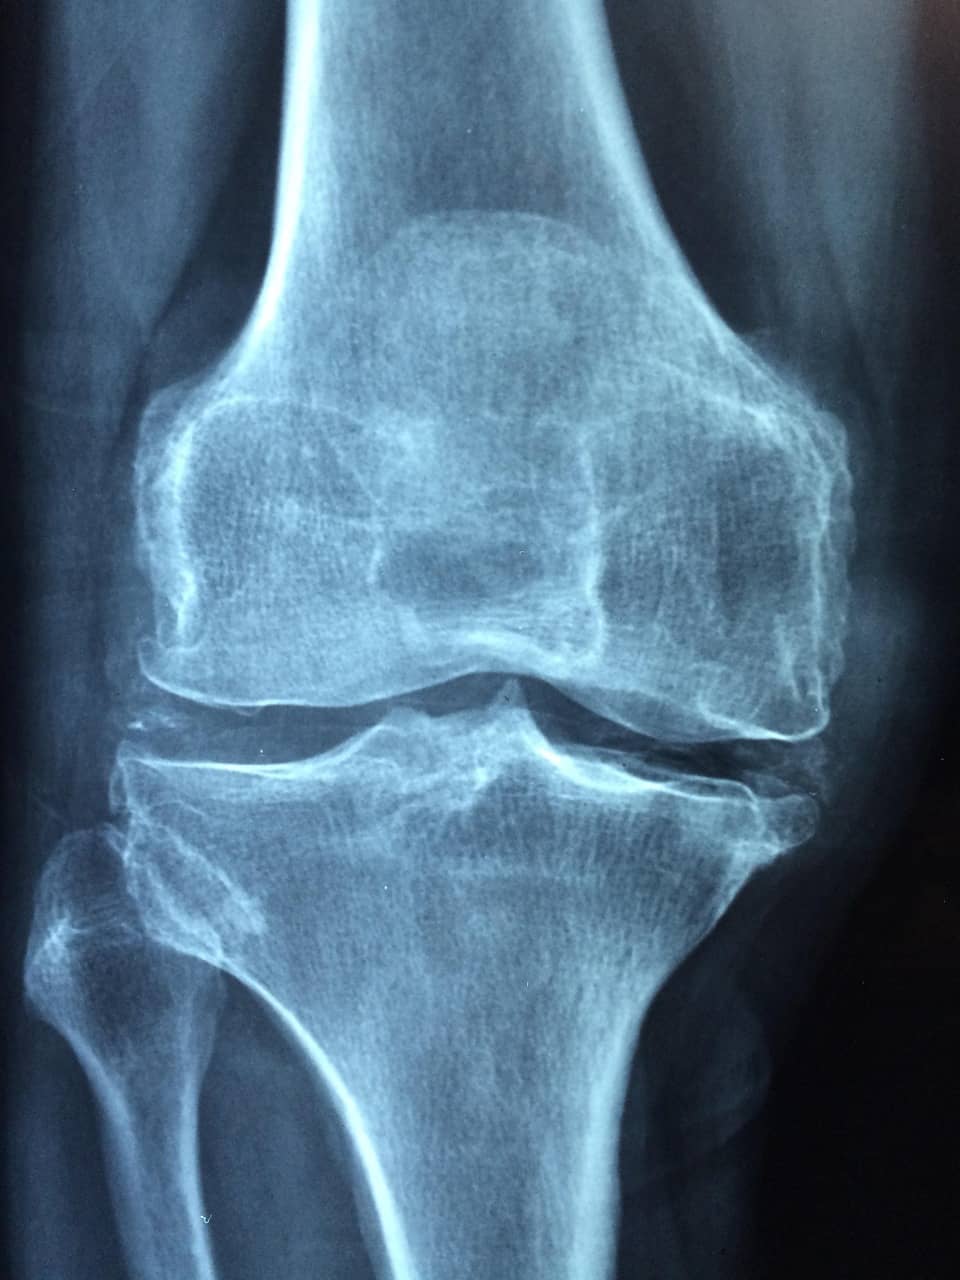

골다공증은 뼈에 작은 구멍이 무수히 많이 생겨 뼈가 스펀지처럼

약해지는 질병입니다. 뼈가 약해지면 아주 가벼운 충격에도 쉽게 골절되죠.